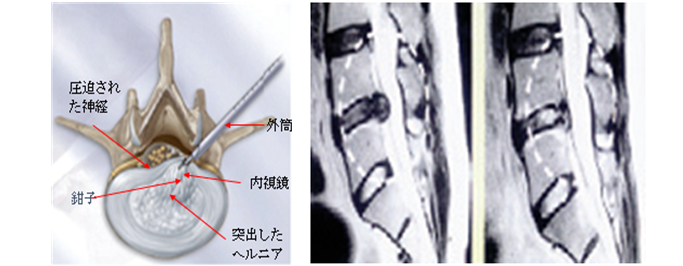

MDCT,MRI検査,超音波検査,骨塩定量(DEXA)を導入し、より細やかな診断が可能になっております。